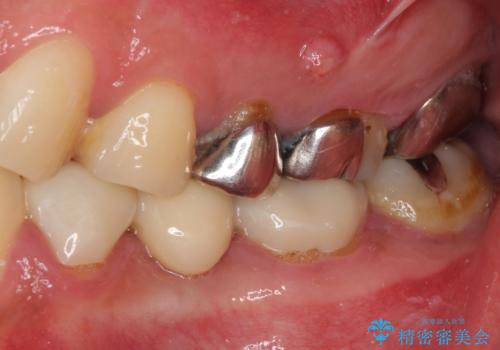

- 奥歯が痛いとのことで来院された患者様です。

歯肉に排膿の痕があり、叩いたり咬んだりすると痛みを感じていました。

根管治療を行い、その後フルジルコニアクラウンにて補綴することとしました。